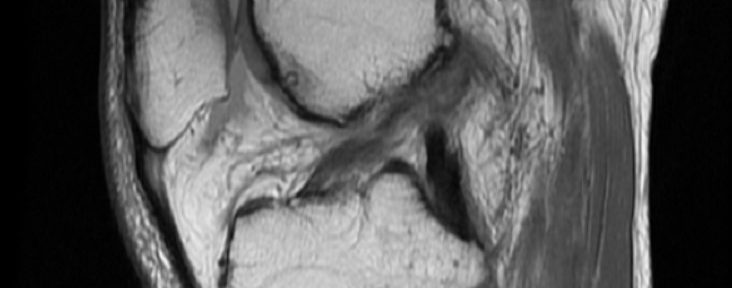

On Dec.28, 2021, he injured his right knee during skiing. On the same day, he was taken to the hospital, and there was no fracture through x-ray. On Jan.13, he was taken to the MRI scanning and diagnoses as:

Complete ACL tear

Buckling of medial meniscus

On Jan.17, he had a surgery for repairing the meniscus, and his knee was immobilized by the cast for three weeks. After the cast was removed, he visited Jun Matsumoto, and he started the Evo-Devo EX. for natural healing of ACL tear. He continued the therapy through face-to-face and online sessions for six months. On August 4, he took the next MRI.

The MRI indicates:

Continuity of ACL fibres